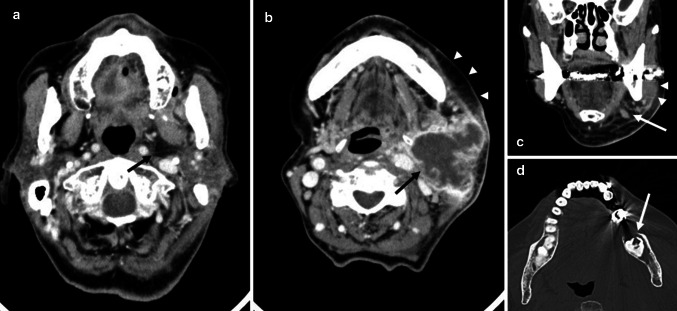

Fig. 2.

A 99-year-old woman with odontogenic infections. a Axial contrast-enhanced CT image demonstrates the spread of odontogenic infections in parapharyngeal space (arrow). b Axial contrast-enhanced CT image demonstrates abscess in submandibular space (arrow) and the spread of odontogenic infections in buccal space (arrowheads). c Coronal contrast-enhanced CT image demonstrates the spread of odontogenic infections in masticator space (arrowheads) and submandibular space (arrow). d. Axial bone-algorithm CT image demonstrates pericoronitis (arrow)